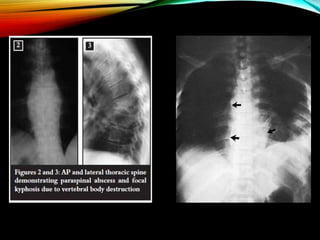

1. X RAY FINDINGS :

• Early changes :-

haziness and local osteoporosis of end

plates of

two adjacent vertebrae

 narrowing of intervertebral disc space.

• Late changes :-

 paravertebral shadow

 ant wedge compression collapse - deformity

 central or concertina collapse

 destruction of post element

X ray changes appear after 3-5 months.

PARA VERTEBRAL

SHADOW- X RAY

1. Cervical

region

- Shadow in Retropharyngeal

space

- V-shaped

shadow

2. Upper

thoracic

mediastinu

m

- Change in contour of tracheal

3. Below 4th

- Fusiform or bird nest

4. Below

D10

5.

Aneurysma

l

phenomen

- Bilateral widening of psoas

-tense thoracic vertebral abscess

showing scalloping effect